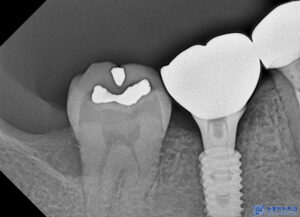

치아를 확인해 보니,

오른쪽 아래 작은 어금니는

이미 예전에 다른 곳에서

신경치료까지 받았던 부분이나

충치와 염증이 발생하였습니다.

이렇게 기존의 재료들을 제거하고

재신경치료를 진행하였습니다.

신경치료를 마무리한 후에는

치아 내부를 안정적으로

보강하는 과정이 필요합니다.

레진을 이용하여

치아의 빈 공간을 채워주었습니다.

치료 후 엑스레이 촬영을 통해

확인한 결과,

뿌리 끝 염증이 이전보다

눈에 띄게 감소한 것을

확인할 수 있었습니다.